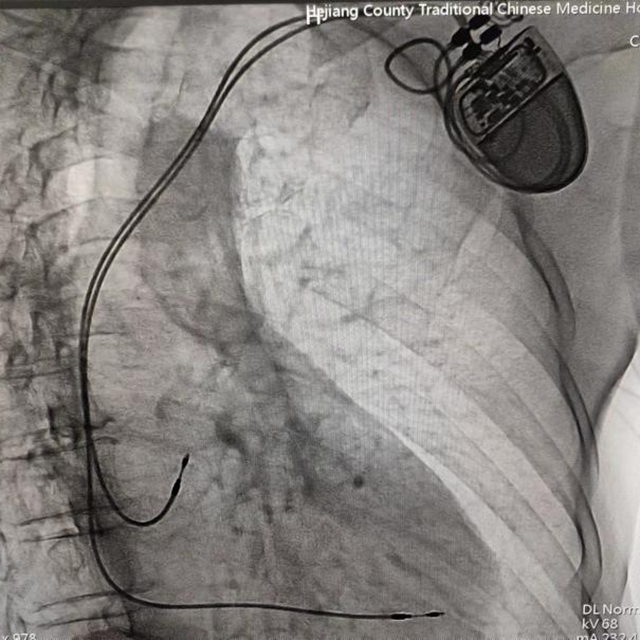

近日,合江县中医医院心血管内科成功为3位高龄心动过缓患者植入人工永久双腔起搏器,实现了医院心脏永久双腔起搏器安置术零突破,为患者心脏装上“保险”!

患者男性,67岁,突发晕厥入院,心电图提示为三度房室传导阻滞。

经心血管内科团队综合评估,确定该患者有行心脏永久人工起搏器植入指征。科室主任黄胜立即与患者家属沟通,并告知相对风险后,家属考虑后,同意心血管内科团队为家属行心脏永久人工起搏器植入手术。

经过充分的术前准备,由心血管内科主任黄胜主刀,在介入医学中心医护团队默契配合下,成功为患者行永久性心脏起搏器植入术。手术历经1小时左右顺利完成,起搏器感知、起搏功能良好,患者生命体征平稳。近日,科室又为两名患者成功开展了此手术。